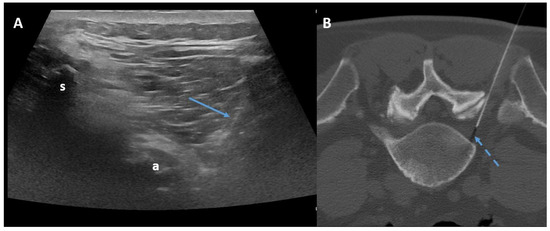

- Napoli, A.; Alfieri, G.; De Maio, A.; Panella, E.; Scipione, R.; Facchini, G.; Albisinni, U.; Spinnato, P.; Nardis, P.G.; Tramutoli, R.; et al. CT-Guided Pulsed Radiofrequency Combined with Steroid Injection for Sciatica from Herniated Disk: A Randomized Trial. Radiology 2023, 307, e221478. [Google Scholar] [CrossRef] [PubMed]